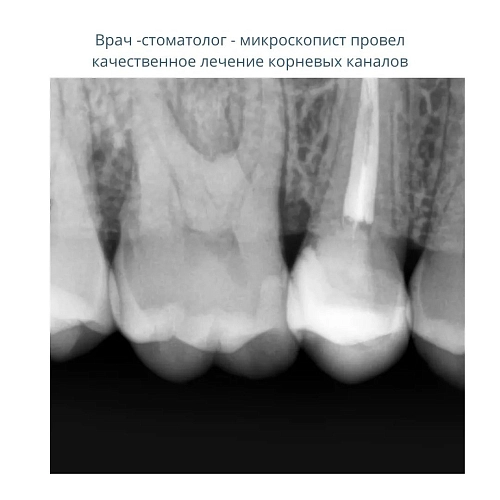

На фото представлен клинический случай

Перелечили корневые каналы под микроскопом и максимально сохранили здоровые ткани.

Установили безметалловую коронку с идеальным прилеганием и потрясающе попали в цвет